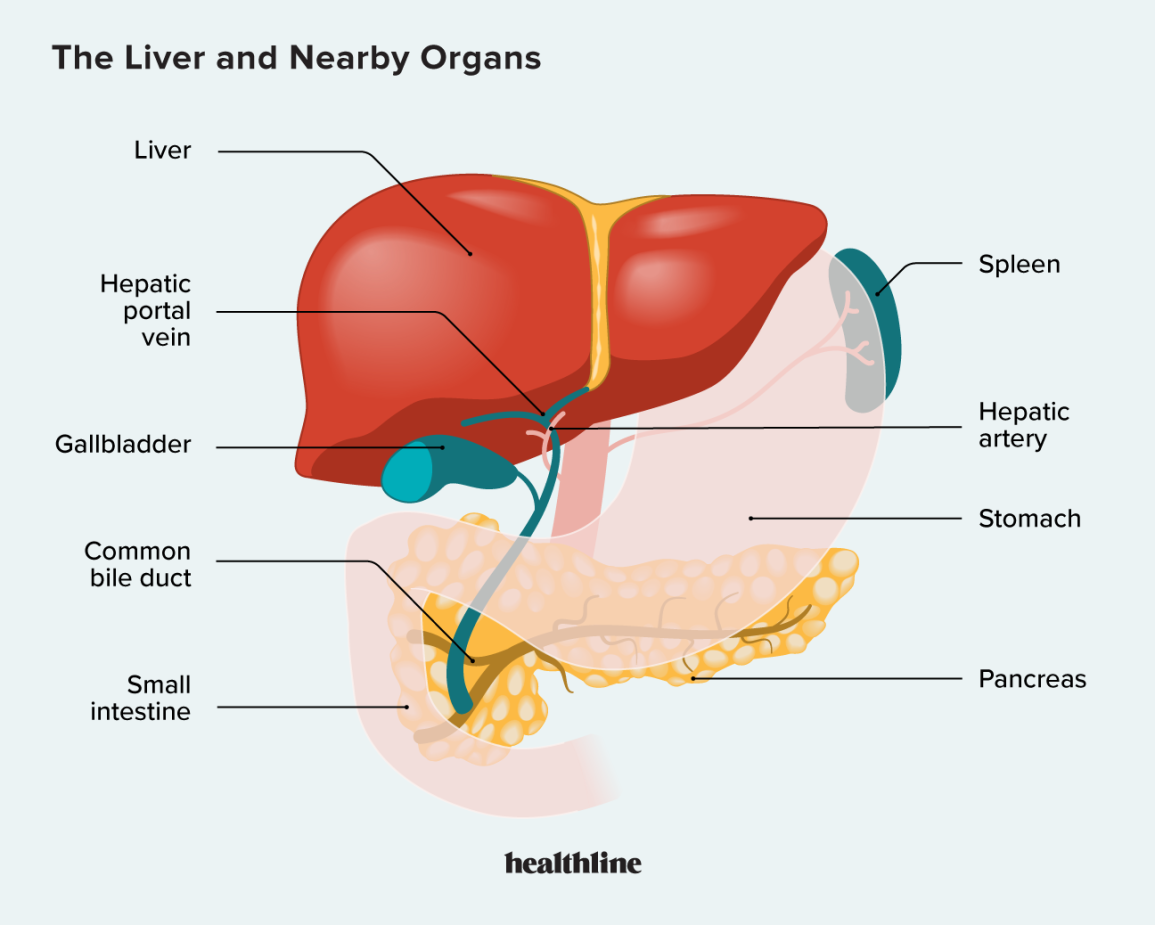

The liver is located in the upper right-hand portion of the abdominal cavity, beneath the diaphragm, and on top of the stomach, right kidney, and intestines

The gallbladder is a small organ located just below your liver in your right upper abdomen. It stores bile, which is a liquid produced in the liver. The gallbladder releases bile into the small bowel to help break down and absorb dietary fats. Normal digestion is possible without a gallbladder.